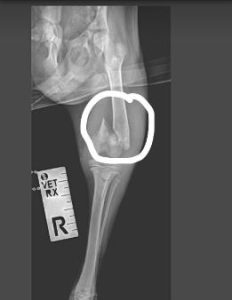

Jamie and his two siblings were found abandoned in a derelict school house. Desperation was etched on their sweet faces and their bodies were full of fleas and their skin covered in demodex. Jamie was found to be less active than his siblings and after x-rays was found to have a fractured femur. He has now had an operation and is recovering from his ordeal alongside his brothers